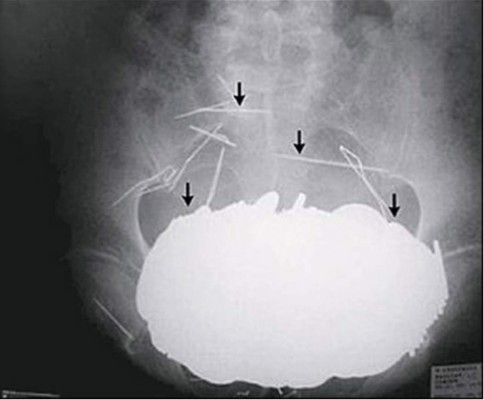

En el estómago de un hombre de 62 años fueron halladas más de 350 monedas de distintos tamaños. El caso ocurrió en Cholet, Francia. En total tenía casi 6 kilos de cuerpos extraños, sobre todo metálicos, incluyendo también collares y agujas. 04/12/2019 - 00:002 / 10 -

Del estómago de un joven sacaron 20 cucharas, 7 cepillos de dientes, 4 tenedores, un anillo y una cadena. El joven, que padece una atrofia cerebral, quedó estable después de las cirugías, dijeron los médicos del hospital de Mansoura, en el norte de Egipto.